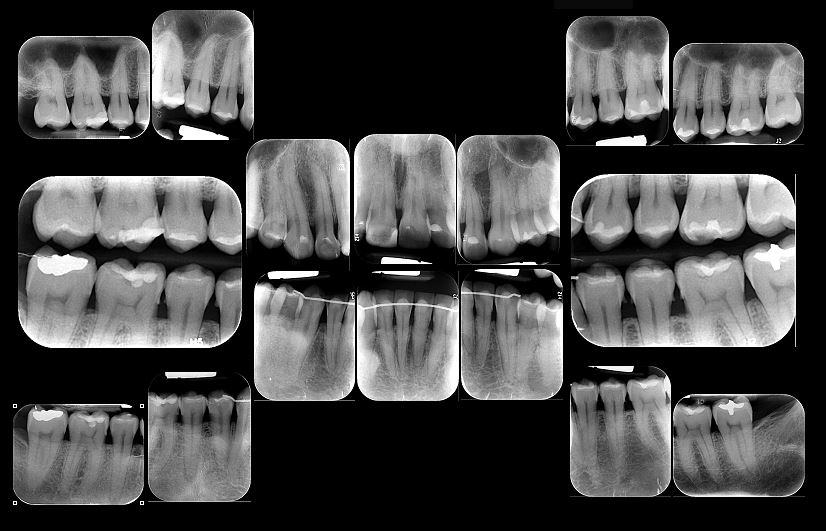

- Radiografía periapical: Es utilizada para evaluar con mayor detalle y definición una zona de interés y sus tejidos circundantes. Permite observar caries, enfermedad periodontal, anomalías dentarias y demás. Entre estos se encuentra la serie periapical que consta de 14 a 16 radiografías periapicales.

Se utilizan principalmente radiografías periapicales, Bite-Wing y oclusales, cada una con funciones específicas para evaluar diferentes estructuras y patologías en la cavidad oral.

La radiografía periapical permite evaluar en detalle una zona de interés y sus tejidos circundantes, ayudando a detectar caries, enfermedad periodontal y anomalías dentarias.